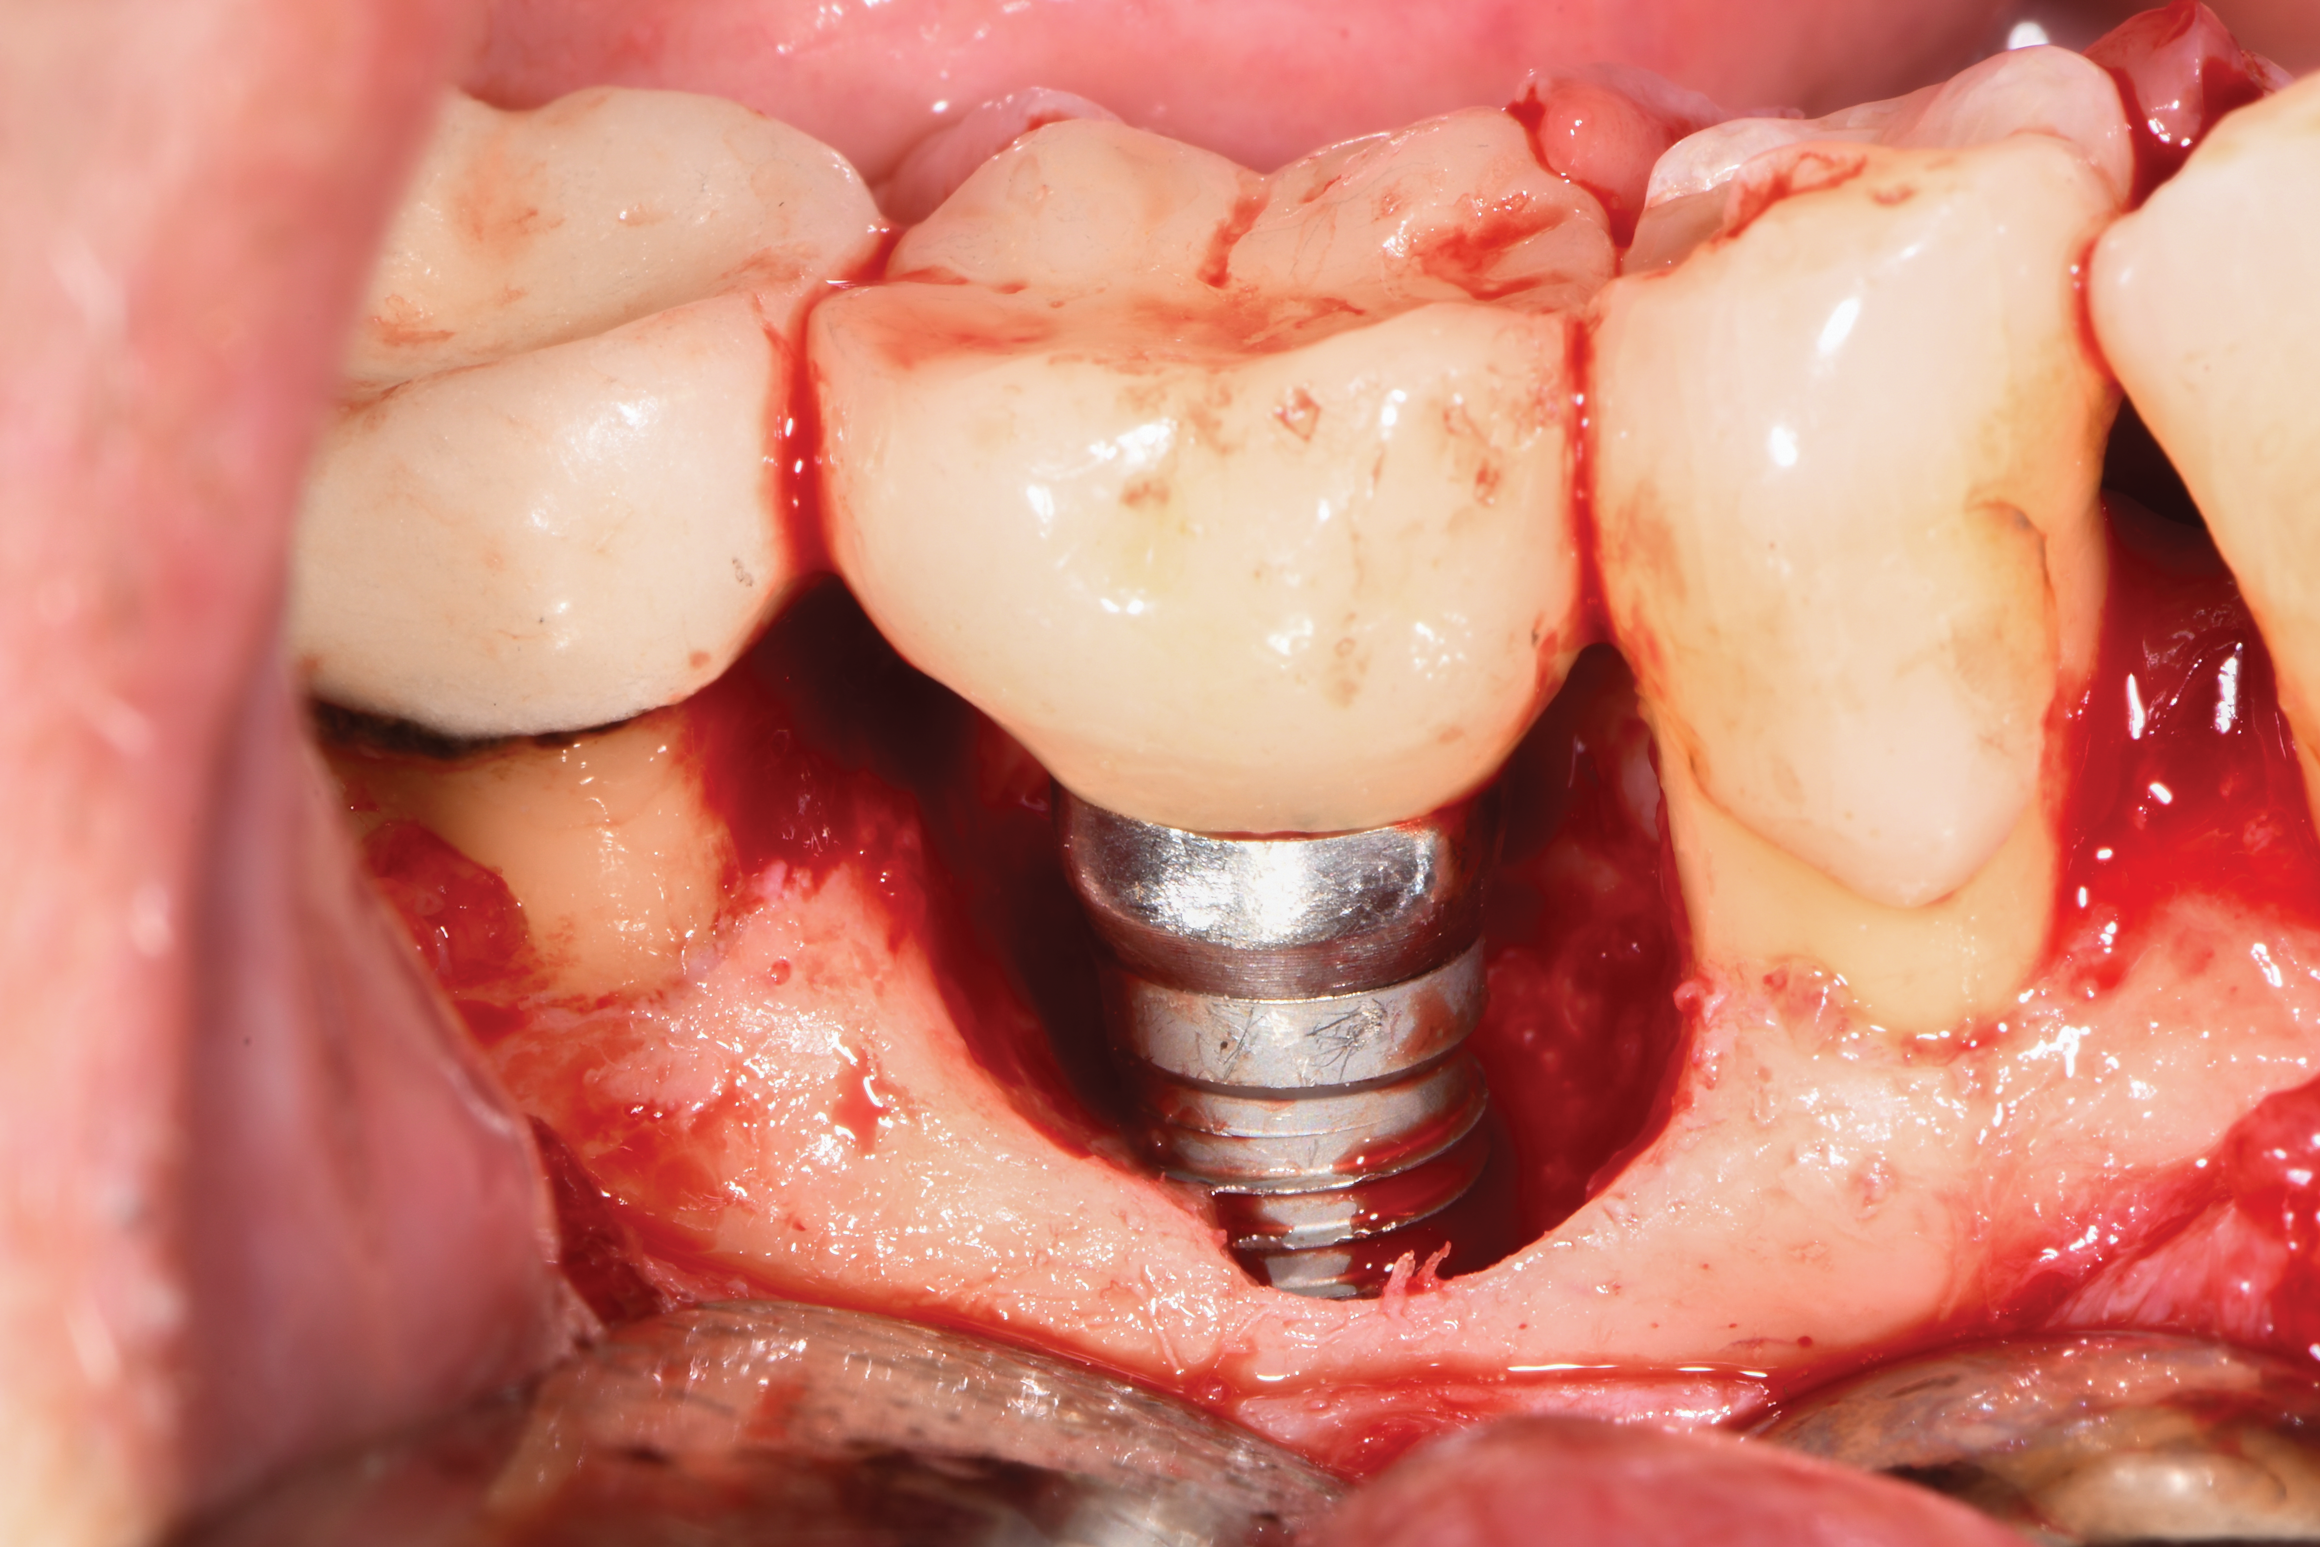

Based on clinical and radiographic examination of the area, the patient was diagnosed with moderate peri-implantitis subcategory A (Figure 10 and Figure 11).19 Pocket depths at this implant ranged up to 9 mm. A surgical approach was planned that included implantoplasty and guided bone regeneration.

After local anesthesia was administered, full-thickness flaps were elevated from the buccal and lingual aspects of tooth No. 27 to the distobuccal and lingual aspects of tooth No. 31. Removal of granulomatous tissue from the implant site allowed visualization of a combination lesion with two walls at the distal and two to three walls at the mesial with a circumferential configuration on the lingual (Figure 12). The surface was initially treated with a 50% solution of citric acid for 30 seconds, which was burnished on with cotton pellets followed by thorough rinsing with sterile saline. This was followed by implantoplasty using 12-fluted followed by 30-fluted surgical-length finishing burs that provided access to the base of the defect. Because the crown was cemented, which obviated access, a matte-like surface could not be achieved; thus, the goal was to reduce the threads and remove the outer affected surface to expose fresh titanium (Figure 13). At this stage, the implant was wiped again with citric acid and rinsed with sterile saline.

Fig 12. The lesion was visualized upon flap reflection. A three- to two-wall lesion on the mesial wrapped to the lingual, while the distal had a two-wall lesion that also extended to the lingual as a moat.

Figure 12